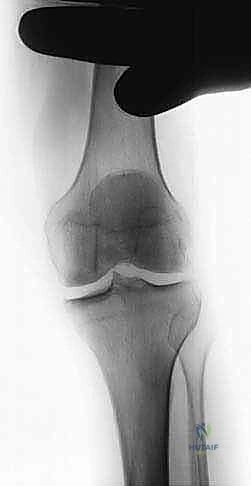

3. الأشعة السينية (X-rays) بوضع الوقوف: وهي الأداة التشخيصية الأهم. يتم أخذ صور أشعة والوزن محمل على الساقين لرؤية المسافة الحقيقية بين العظام. في حالة الخشونة المتقدمة، تظهر الأشعة غيابًا تامًا للمسافة المفصلية في الجزء الداخلي (Bone-on-bone).

صورة طبية: استبدال مفصل الركبة الجزئي (UKA): دليل شامل لمرضى خشونة الركبة الداخلية مع الأستاذ الدكتور محمد هطيف